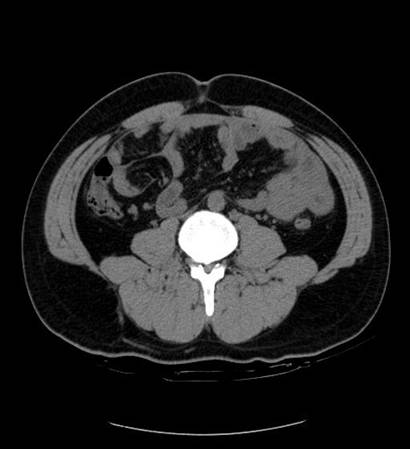

以下是引用zsl6918在2007-6-22 21:08:00的发言:[br]病史较长,反复发作,基本排除恶性病变,腹部定位像可见是小肠梗阻征象,原因无非是肠源性,血管性和神经性的,肠源性的在排除占位后应想到 肠旋转不良的可能,血管性的应想到肠系膜血管的栓塞,神经性的要想到植物神经功能紊乱的可能,本病例应该强化检查帮助诊断,个人感觉旋转不良可能性大。

以下是引用青莲居士在2007-6-24 12:27:00的发言:[br]肠梗阻[br]肝内胆管结石